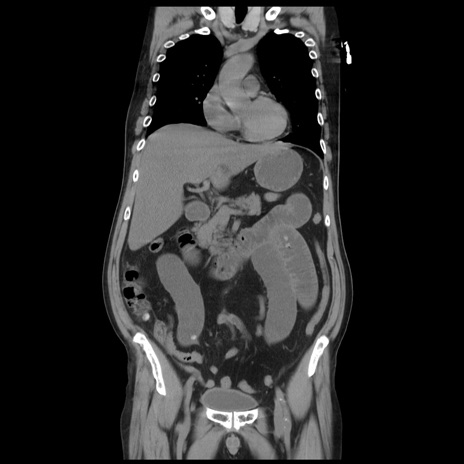

症例20(冠状断像)

【症例】 60歳代男性

【主訴】 腹部膨満、嘔吐

【現病歴】5日前頃より倦怠感を認め食事量減少し4日前の朝嘔吐、食事摂取困難となった。 3日前近医受診し点滴施行され整腸剤などを処方された。 当日他院を受診し、腹部膨満著明、炎症反応の上昇(CRP10.8、WBC11200)あり、紹介受診となる。

【身体所見】 意識JCS1 受け答えがはっきりしないBP 111/57mHg、 P 67bpm、、BT35.2°C、SpO2 97%(RA)、 腹部:膨隆、打診で鼓音あり、全体的に圧痛有り、腸蠕動音(-)、反跳痛ははっきりせず。

【データ】WBC 11400、CRP 14.20